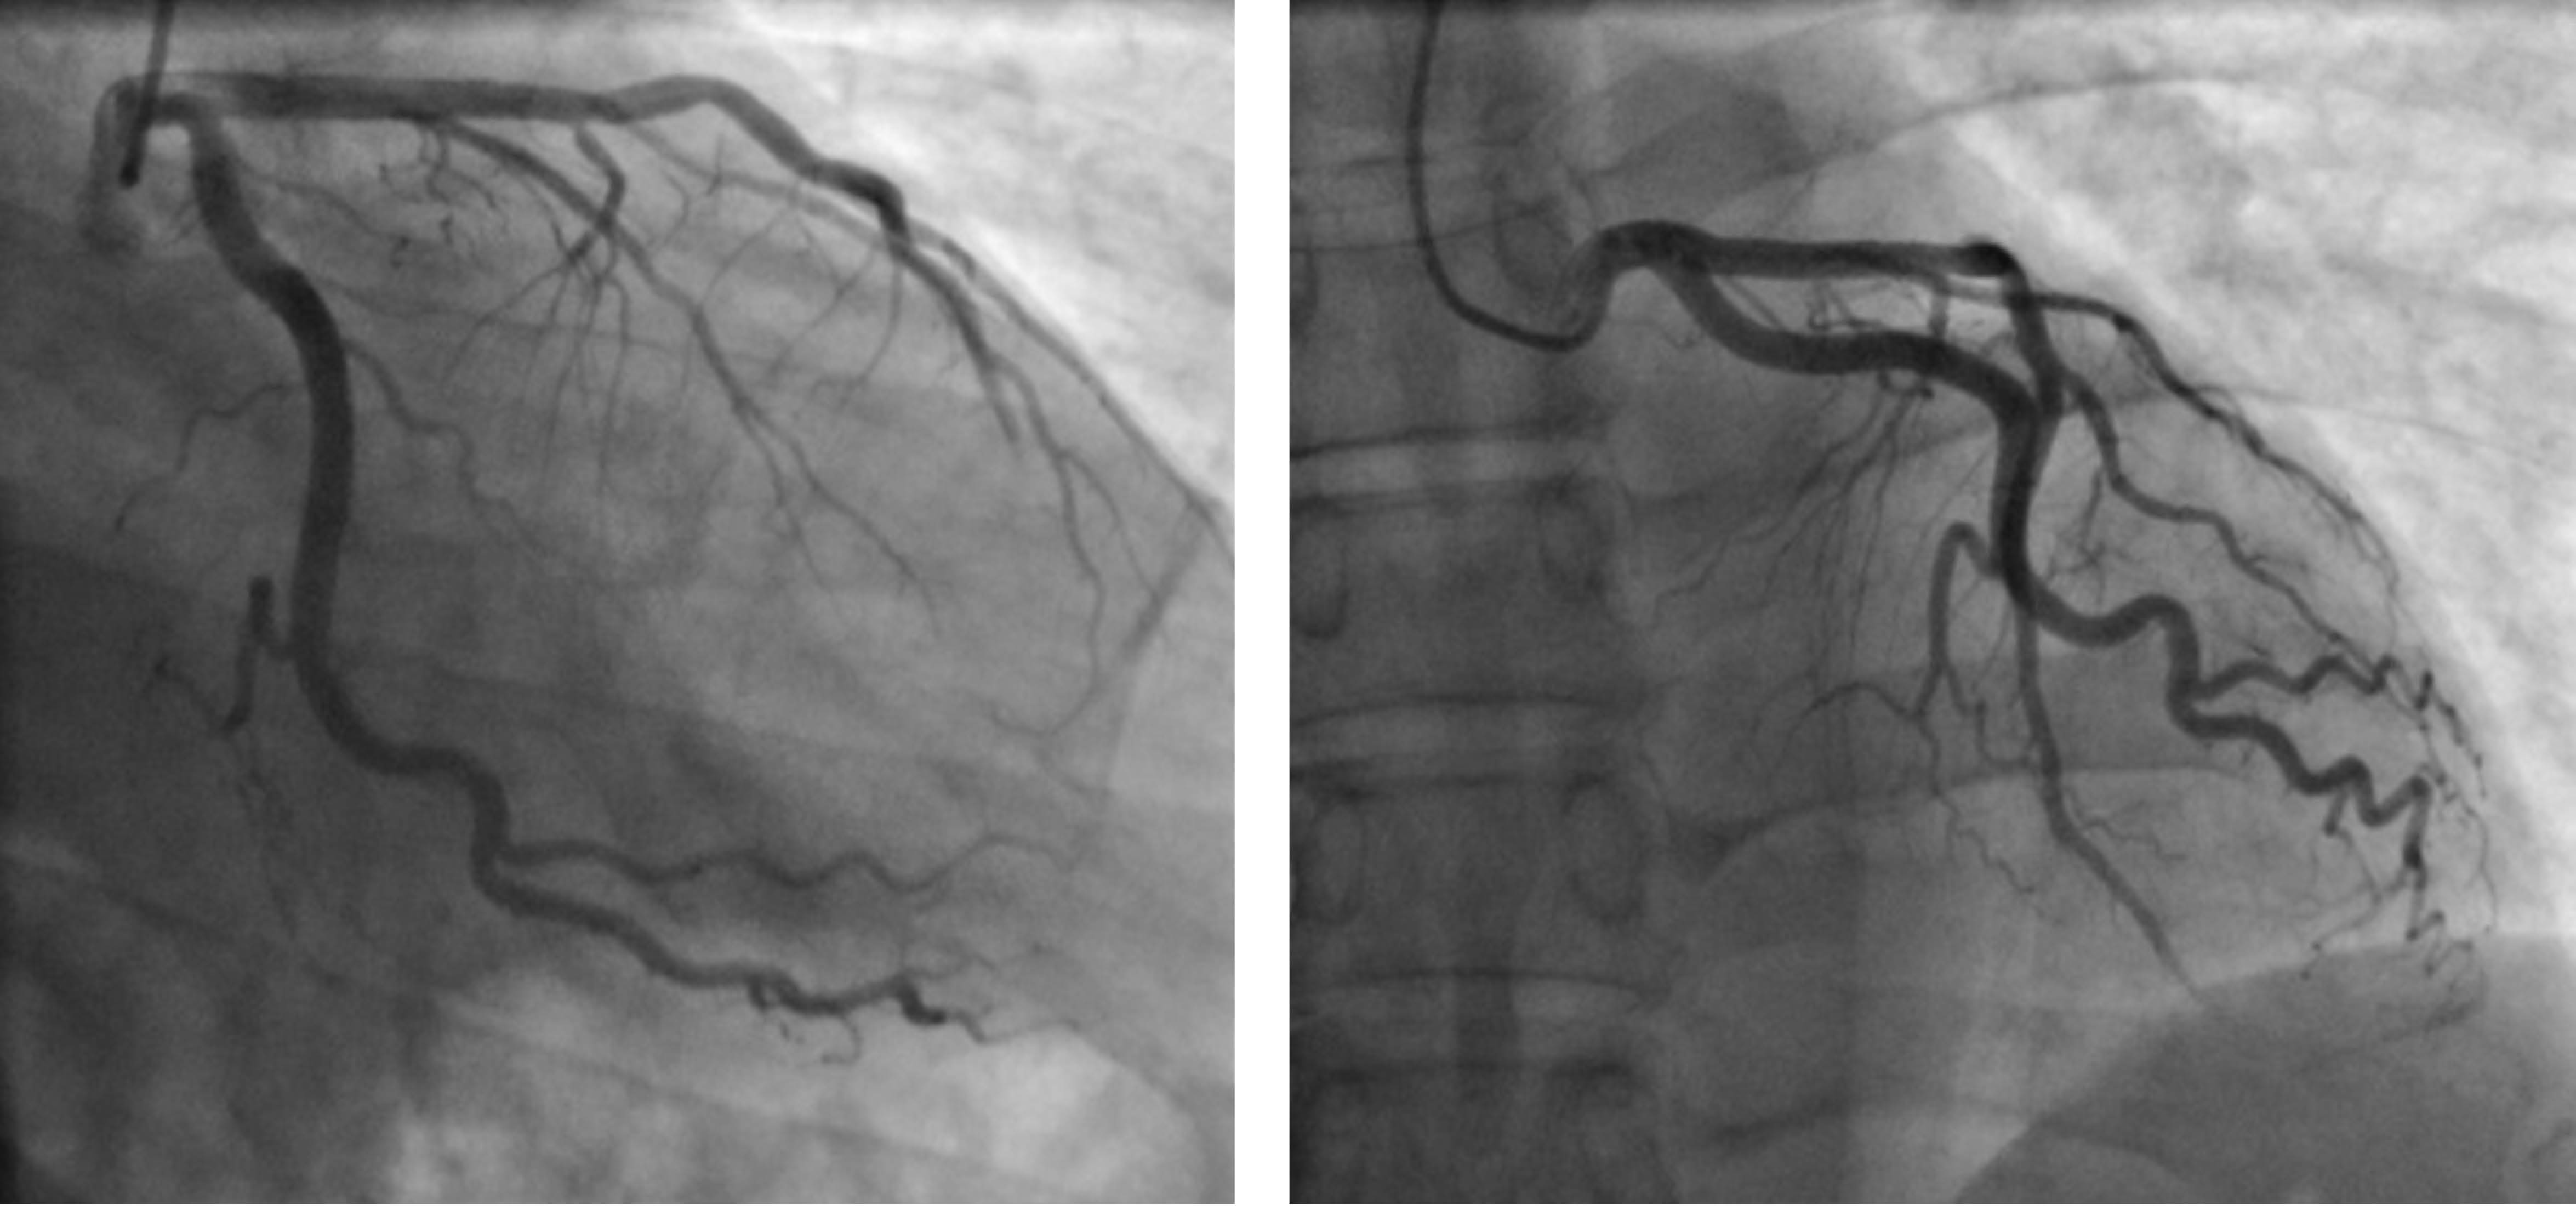

Divertículo ventricular congénito izquierdo aislado en adulto: un hallazgo inusual en infarto de miocardio asociado a cocaína

El divertículo ventricular congénito izquierdo (DVCI) consiste en una bolsa de salida de endocardio, miocardio y pericardio, que a menudo se presenta como una proyección de la pared libre del ventrículo, con un cuello estrecho que conecta la cavidad con el ventrículo propiamente dicho. Aunque a menudo se asocia con otras anomalías congénitas cardiacas y extracardiacas, también puede presentarse solo, como un hallazgo incidental en pacientes adultos. Debido a su baja prevalencia general y variabilidad en la presentación, aún no se ha definido un tratamiento estandarizado. Presentamos el caso de un paciente adulto con infarto de miocardio (IM) asociado a cocaína, en el que se evidenció un DVCI septal mediante angio-TC coronaria. Se descartaron otras anomalías cardiacas y el paciente respondió bien al tratamiento médico tras el cateterismo cardiaco; por lo que se prefirió el seguimiento médico y no la cirugía.

Figura 1